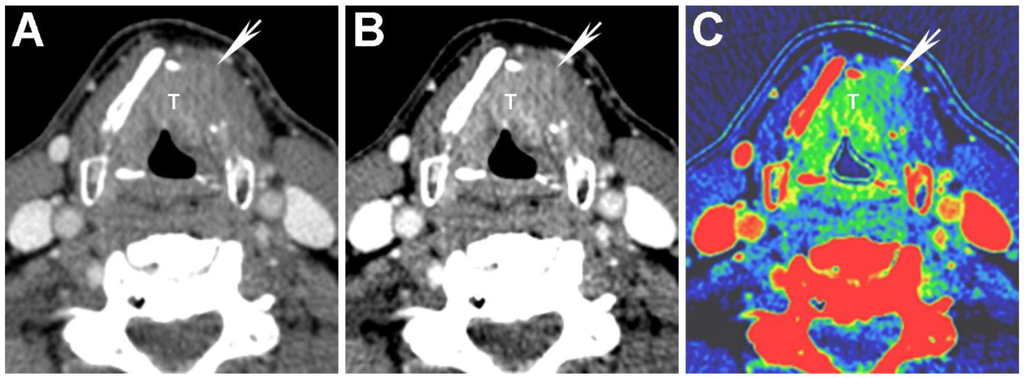

Figure 5. High energy virtual monochromatic images (VMIs) for evaluation of non-ossified thyroid cartilage (NOTC). 140 keV image from the same patient as in Figure 3 is shown. The laryngeal tumor invades the left thyroid cartilage, and the invaded portion appears as a relatively low density defect (double arrows) because of suppression of iodine density within the enhancing tumor on high keV images (compare to Figure 3A,B). In this case, there is partial non-ossification of the thyroid cartilage on the left posteriorly. Note the preserved high attenuation of the NOTC (single arrow). There is clear attenuation difference between normal NOTC and tumor on the 140 keV image but the density on conventional single energy equivalent 65 keV image is nearly identical (compare to Figure 3A). It is noteworthy that the tumor itself is not well seen on the 140 keV images, and these VMIs should be used in conjunction with the 65 and/or 40 keV VMIs and not in isolation.